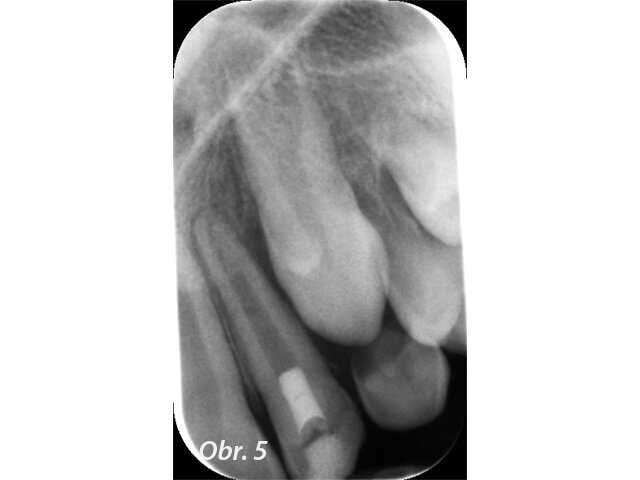

U pacienta v 10 letech byla pro úrazovou ztrátu vitality provedena revaskularizace na zubu 22. Po 2týdenní aplikaci kombinace antibiotik do prostoru pouze chemicky dekontaminovaného kořene byl po vyvolání krvácení aplikován prostředek PRGF a kořen uzavřen pomocí MTA. Zub byl rekonstruován kompozitem. Na kontrole po 5 letech je viditelně zvětšený objem tkáně kořene a absence projasnění. (Obr. 4–6)

Častou komplikací (téměř inherentní součástí) tohoto ošetření je zbarvení korunek ošetřených zubů, které je následně po vytvoření kořenové tkáně nutno řešit vnitřním bělením (obr. 7).